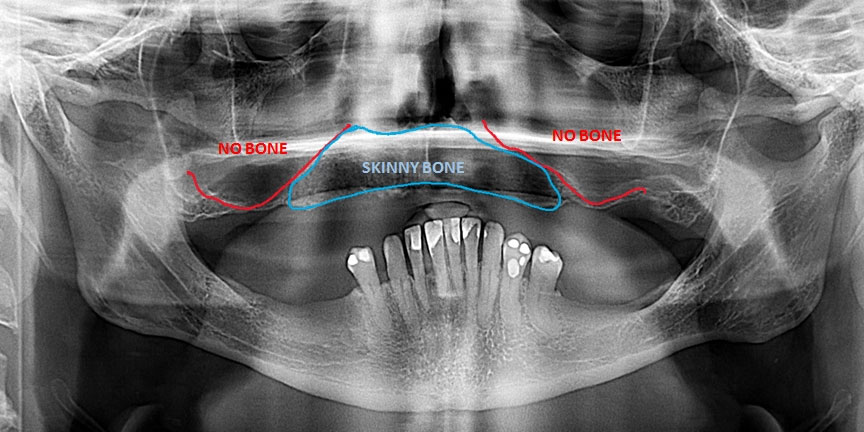

Severe Bone Loss

ImageImage